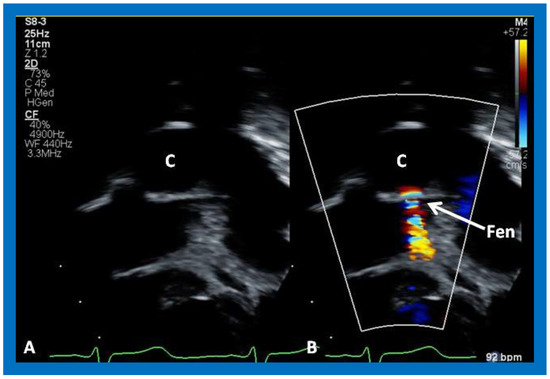

Following bidirectional Glenn, the LV size is likely to decrease (normalize) and LV should maintain normal systolic function. This is because of decreased LV volume overload following bidirectional Glenn and the removal of aorto–pulmonary shunt. The 2D imaging of the bidirectional Glenn is difficult to accomplish, but color flow imaging (Figure 25A, Figure 26B, and Figure 27B) from a suprasternal notch or high parasternal views will help image the bidirectional Glenn. Low pulsed Doppler velocity across the superior vena cava (SVC)–PA junction (Figure 25B and Figure 26C) would indicate no obstruction. Turbulent and high velocity Doppler flow suggests the obstruction of the bidirectional Glenn shunt. The size of the branch PAs may be assessed with a combination of 2D and color flow imaging (Figure 26, Figure 27 and Figure 28).

Figure 25. Selected video frames from suprasternal notch view demonstrating bidirectional Glenn shunt; the superior vena cava (SVC) is shown emptying into the right (RPA) and left (LPA) pulmonary arteries by color flow imaging (A). Low Doppler flow velocity across the shunt (B) indicates unobstructed Glenn.

Applsci 11 09472 g025

Figure 26. (A,B) Selected video frames from suprasternal notch view demonstrating bidirectional Glenn shunt. In (A), the right (RPA) and left (LPA) pulmonary arteries are shown by 2D. The superior vena cava (SVC) was not clearly seen. In (B), the SVC is shown emptying into the RPA by color Doppler (B). The LPA did not show color flow because it was in a different plane of imaging than RPA, but is seen by 2D (B). (C) Low Doppler flow velocity across the Glenn shunt indicates unobstructed flow.

Applsci 11 09472 g026

Figure 27. Selected video frames from suprasternal notch view demonstrating bidirectional Glenn shunt; the superior vena cava (SVC) is shown emptying into the right (RPA) and left (LPA) pulmonary arteries by two dimensional (A) and color flow imaging (B). Both RPA and LPA are seen with color in contrast to that seen in Figure 26, probably related to both pulmonary arteries are in a similar echo plane.